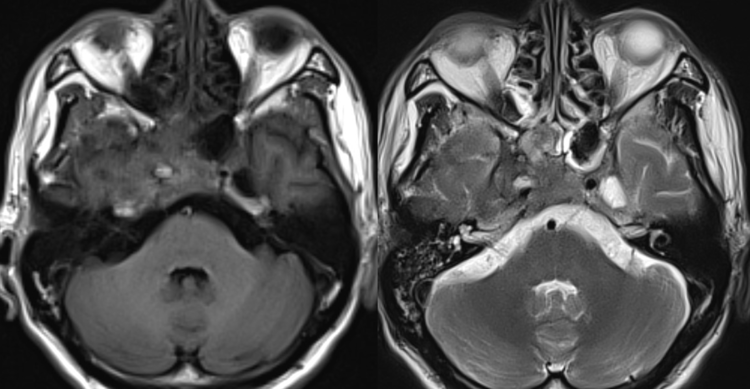

之前经常性头痛,最近头痛明显加重,程度无法忍受,伴有右眼视力急剧下降。行核磁检查发现右侧海绵窦区占位病变,MRA发现局部轻度扩张,考虑动脉瘤,瘤内存在大量血栓。遂行DSA检查,发现右侧海绵窦段动脉瘤样改变,瘤体不大,病变远近端颈内动脉均存在严重狭窄。

术前MRA提示海绵窦部位血管局限性狭窄扩张,符合动脉瘤的改变。

颈内动脉海绵窦动脉瘤的诊断明确,虽然造影显示DSA动脉瘤很小,通过症状病史结合影像,考虑动脉瘤为大型病变,近期可能急性血栓形成,导致动脉瘤体增大,对海绵窦结构和视神经产生压迫,引起出现头痛和视力下降等症状,但是诱发急性血栓形成的因素无法确认,瘤体远近端的狭窄是动脉硬化性还是血栓生长的结果,从影像上无法确认。